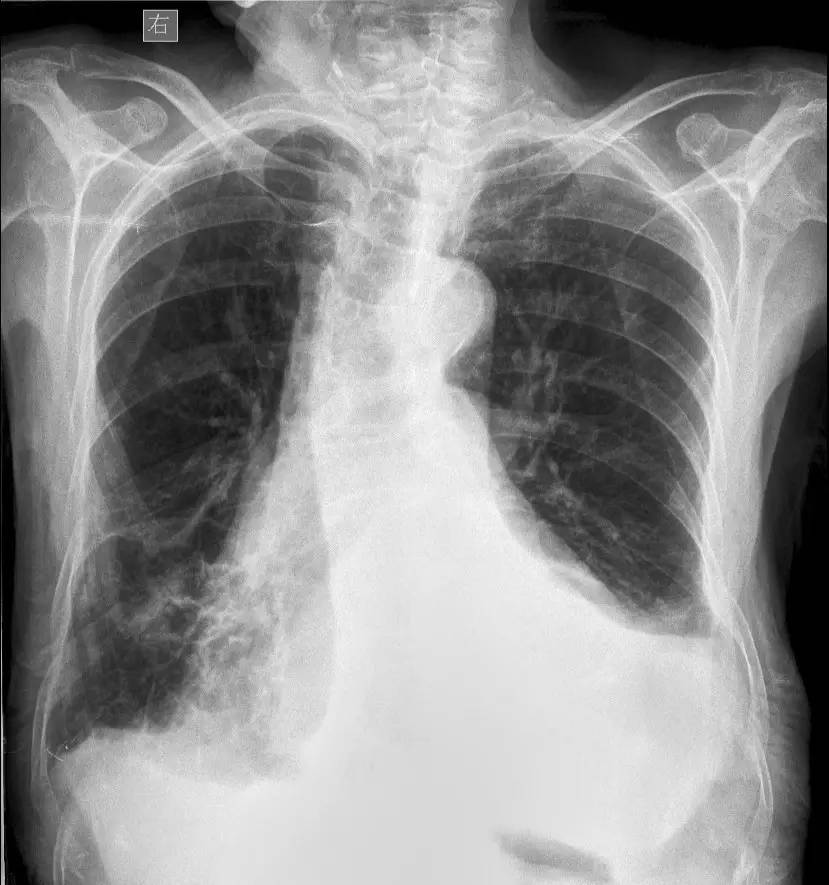

>>>>病例1:男 82岁 体检,患者自述无任何不适。

左下肺最有可能的诊断是?

A.包裹性积液

B.胸膜增厚

C.胸腔积液

D.心包脂肪垫